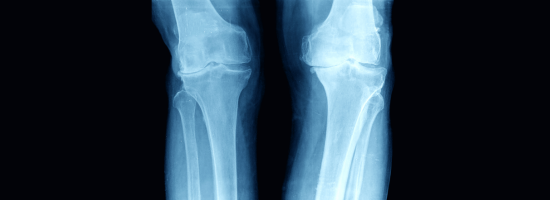

Your knees carry you through every stride, squat, and step. When pain, stiffness, or injury interferes with your mobility, it affects more than just your joints—it affects your life. At East Alabama Health, we specialize in diagnosing and treating a wide range of knee conditions so you can get back to doing what you love—without pain holding you back.

Common Knee Conditions We Treat